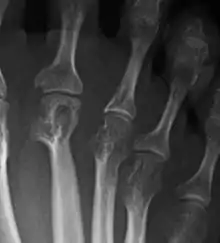

La artritis o inflamación de las articulaciones es la manifestación fundamental de la artritis reumatoide. Las articulaciones afectadas están hinchadas, calientes, dolorosas y rígidas, en especial al levantarse por la mañana o tras el reposo prolongado. Al principio pueden estar afectadas solo una o varias articulaciones, pero progresivamente se van sumando más articulaciones inflamadas —poliartritis—, siendo las que con más frecuencia se afectan las pequeñas articulaciones de las manos y los pies, aunque también es frecuente la afectación de otras articulaciones más grandes como los codos, los hombros, las rodillas o los tobillos.[48] La rigidez matinal es, con frecuencia, un dato destacado de la enfermedad y suele durar más de una hora. Estos datos ayudan a distinguir a la artritis reumatoide de otros problemas no inflamatorios de las articulaciones, como la artrosis u otros tipos de artritis. Las articulaciones se afectan habitualmente de un modo simétrico —afectando articulaciones semejantes en ambos lados del cuerpo—.[49] A medida que la enfermedad progresa, la inflamación articular causa erosiones y destrucción de las superficies articulares y daños tendinosos. Los dedos de las manos pueden sufrir diversas deformidades dependiendo de qué articulaciones y estructuras son las más lesionadas. Son deformidades típicas de la artritis reumatoide evolucionada los dedos en cuello de cisne, la deformidad en ráfaga cubital, la deformidad en boutonniere y el pulgar en Z.[48] La inflamación articular mantenida puede originar daños estructurales en las articulaciones, causando deformidad y pérdida funcional de la articulación afectada.[50][51]

La radiografía convencional es la técnica de imagen estándar de la artritis reumatoide. Los primeros signos radiológicos son la osteoporosis yuxtaarticular y el aumento de partes blandas. Estos cambios se siguen de la disminución del espacio articular, que corresponde a la pérdida de cartílago articular, y la aparición de erosiones óseas en las zonas adyacentes al cartílago articular. El tiempo mínimo para la detección de cambios estructurales en las radiografías está entre 6 y 12 meses, detectándose erosiones radiológicamente en el 50% de los pacientes en el primer año de la enfermedad.[49] En la práctica clínica se utilizan las radiografías para el diagnóstico de la enfermedad, para valorar la gravedad del daño articular y para evaluar su progresión. El ultrasonido y la resonancia magnética son técnicas más sensibles que la radiología convencional.